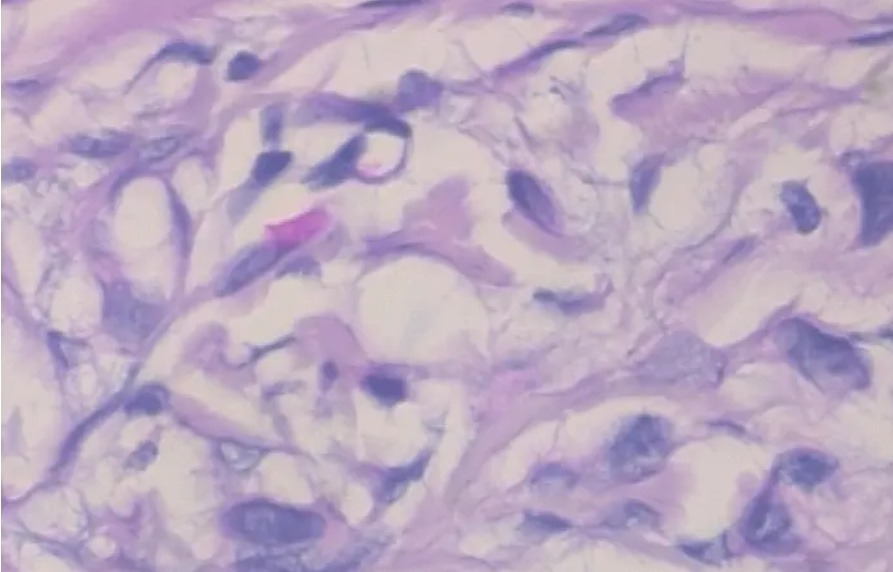

3.2 病变样本

在本博客中,作为博主的我展示了如何通过结合卷积神经网络与迁移学习的方法,在一组乳腺癌显微图像数据集上实现良性和恶性两类肿瘤的区分,并旨在为读者提供参考与指导。